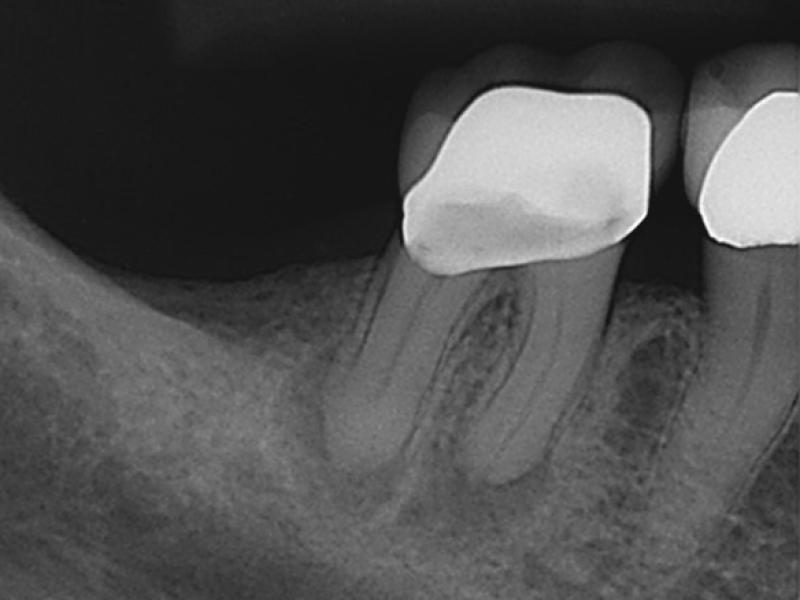

Calcified Canals with Healing Evidence

Recall